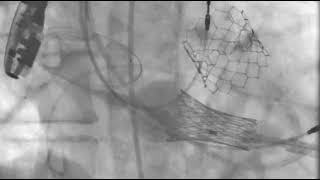

Video 5

Transapical transcatheter mitral valve replacement.